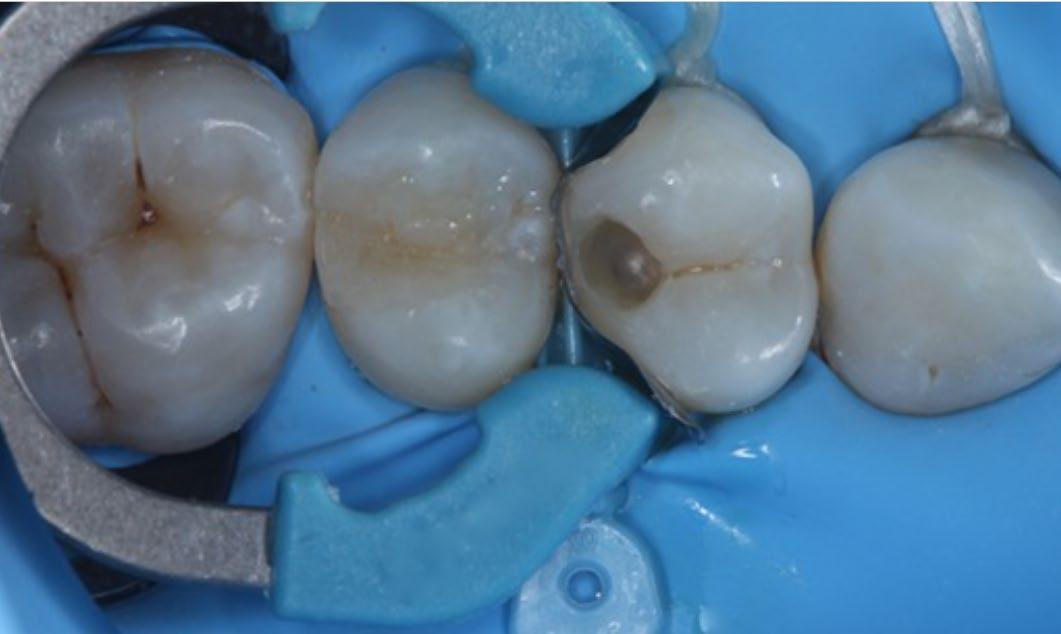

Fig. 1: Initial situation. Fig. 2: X-ray showed hidden caries at the distal side of the upper first pre-molar. Fig. 3: Isolation with rubber dam. Fig. 4: Preparation. Hidden Proximal Caries | Posterior continues next page >>>

Fig. 5: Selective enamel etch. Phosphoric acid gel was applied for 15 seconds, rinsed and lightly dried. Fig. 6: Adhesive was applied on dentin, rubbed in for 20 seconds, air dried for 5 seconds and light cured for 10 seconds.* Hidden Proximal Caries | Posterior continues next page >>> Fig. 7: After adaptation of the matrix system, the first layer of 3M™ Filtek™ Universal Restorative, shade A2, was placed. Fig. 8: Placement of the restoration is completed.